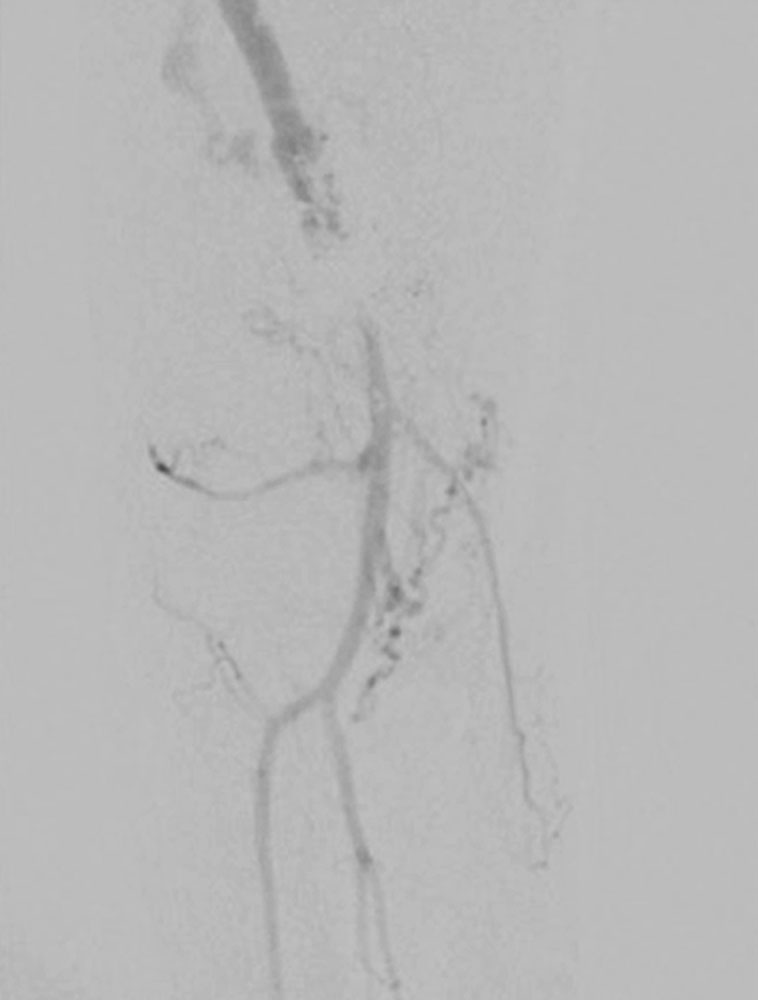

Inzwischen werden resezierende Verfahren an den Gefäßen üblicherweise erst nach oder in Kombination mit endovaskulären Techniken eingesetzt.

Operative Verfahren ergänzen bei Bedarf die endovaskuläre Therapie oder schaffen Zugangswege für die Kathetertechniken.